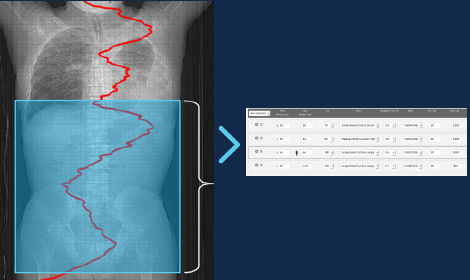

Smart Plan

Smart Plan verwendet die Scout-Bilder, um automatisch den richtigen Scan-Bereich für Kopf-, Brust-, Bauch- und Becken-Scans sowie Untersuchungen in mehreren Gruppen anzuzeigen.

Smart Plan-Funktionen

• Erstellt einen Start-/Endscanpunkt und einen DFOV-Vorschlag für bestimmte Anatomien basierend auf Scout-Bildern

• Unterstützt Kopf-, Brust-, Bauch- und Beckenscans

• Unterstützt die Erfassung mehrerer Gruppen wie Brust/Bauch, Bauch/Becken und Brust/Bauch/Becken

GEHCEffortlessWorkflowScanImage2

GEHCEffortlessWorkflowScanImage3